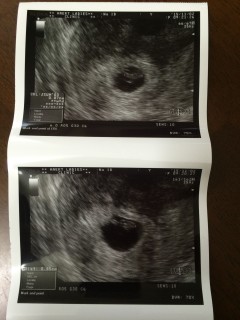

流産を2回、3回目の妊娠です,7w1d、つわりはありません。その分不安ですが9、6mm今度こそ育ちますように

初めての検診から2週間後の2回目の検診。 心配だったけど胎嚢が2センチくらいになり、あかちゃんは0.89センチ。 心臓動いてるのわかりますかー?と先生が言ってるけどわからず。ズームしてもらってやっとピカピカ白黒白黒動いてるのがわかりました。 私の体に命が宿ってるのだなーと実感。卵子から命の誕生の神秘を感じました。 あかちゃんの形はよくわからず、モヤモヤっとしたかたまりでした。 次の検診も2週間後。次は予定日を確定するらしい。

心拍も確認できました◎ 赤ちゃんの大きさは11.2mmとのこと。 前回、8wになっても胎嚢しか確認できず9wで稽留流産だったので、赤ちゃんの姿が見えて心臓が動いているのを見た瞬間思わず涙が溢れました(;_;) 先生から良かったですね、よく頑張りましたね、と言われてまた泣けてきました。 小さくてとてもとても可愛かったです!!